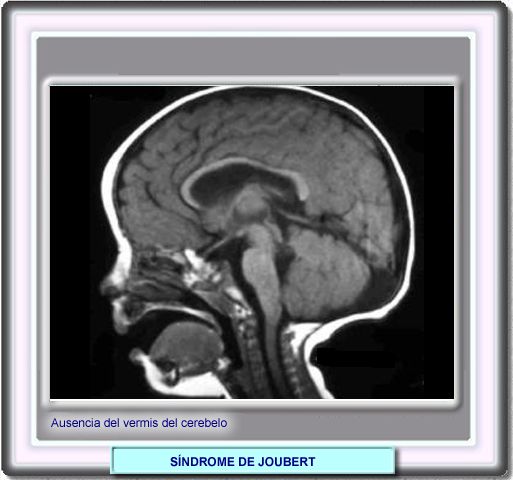

Síndrome de Joubert

Agenesia o hipoplasia del vermis cerebeloso. La fosa posterior conserva su tamaño normal o es pequeña. La tienda del cerebelo no está elevada.